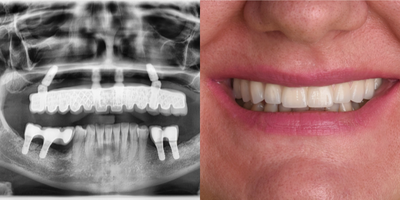

25-34 year old man treated with Dental Bone Graft, Dental Implants, Smile Makeover

Our patient had hopeless teeth in his upper jaw. Also high smile line was present which made the case difficult to achieve a good aesthetics. After digital analysis by the use of 3D CT, bone reduction, extraction of all hopeless teeth and placement of 8 implants was planned. After a 3 months of period, permanent fixed prosthesis has been delivered.